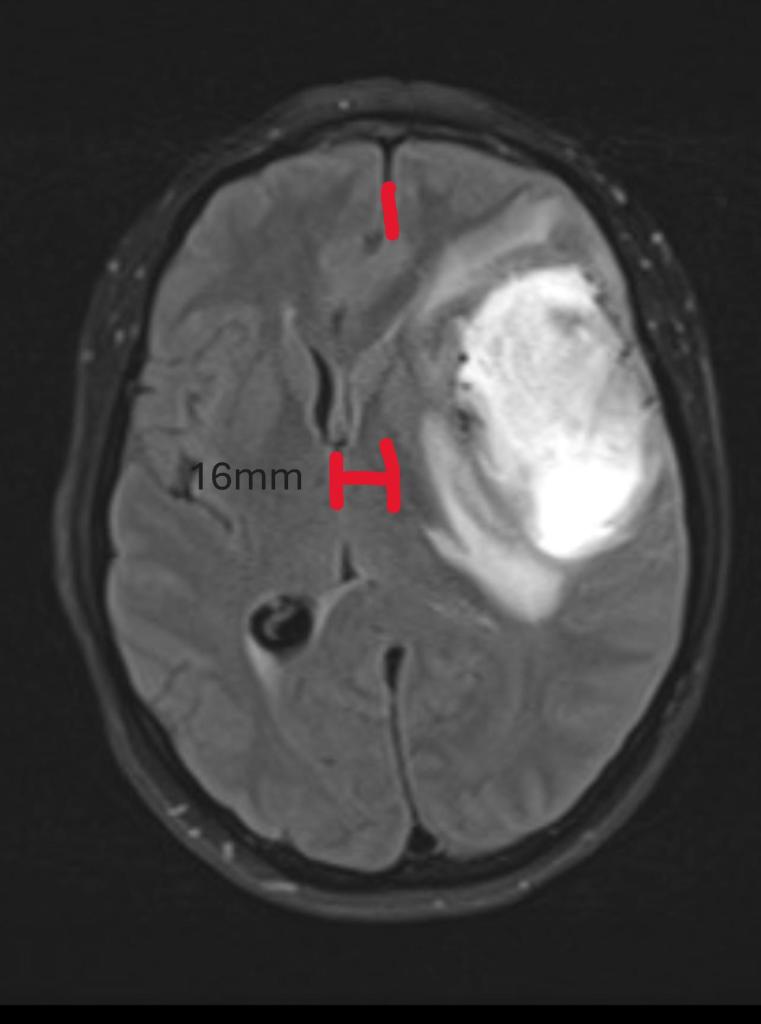

He explained that there was a “mass” in her brain and even showed us the images. He showed us what the MRI displayed as a “mass” on the right-hand side of Laura’s brain, and it was shifting her midline about 16mm to the left. It was so big that it was pushing on her brain and eye, and the pressure alone was causing her headaches. The estimate of its length was about 7 or 8cm long. That’s about 2.7 – 3.1 inches.

Above is the picture of the of the “mass”. I’m not calling it a tumor yet since we didn’t know definitively what it was at this point. The “mass” is the white colored area, and you can see the midline shifted over to the left. We will show the “after” images in a later post. There should be more “texture” than the picture above is showing, but much of it is compressed by the tumor so it doesn’t show up as a normal looking brain.